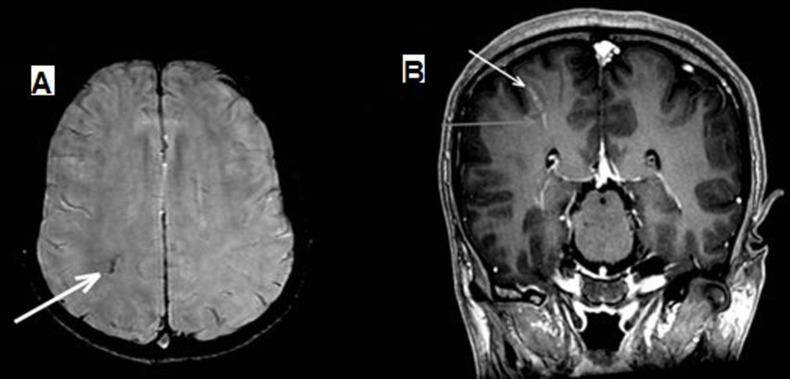

Methods: A record-based study was performed retrospectively in Radiology department at our Hospital in Eastern region of Saudi Arabia, from Jan. 2019-2024. Adult patients for whom MRI brains were conducted for epilepsy work-up with added SWAN (susceptibility weighted angiography) sequence were considered. Imaging proven cases of space occupying lesions in the brain, post-injury, and post-interventional cases were not taken. A venous angioma (or malformation) was documented when a tuft of veins drained to a larger vein (traversing through cortex or reaching under ependymal layer), appeared low signal structure on SWAN image, and enhanced on contrast-enhanced sequence. Consensus reporting was made by 2 experienced neuroradiologists. The usefulness of the SWAN sequence in the detection of venous malformation determined if the visualized abnormality was found to be related to a focus resulting in abnormal waves on the brain electroencephalography. This observation was compared to the accidently found such malformations that were seen in epileptic patients with normal EEGs (control group). Fisher's Exact test was applied and a P-value of <0.05 was taken as statistically significant for an association.

Results: Total number of patients was 114; 65 females (57%) and 49 males (43%), with an average age of 31.4 (range, 15-50). The SWAN found venous angiomas in 34 (29.8%), and 8 were responsible for abnormal electroencephalograms while neither of the 3 accidently detected venous malformations in the control with normal EEGs (p-value=0.001).

Conclusion: An added SWAN sequence with conventional MRI brain imaging for patients with seizures can assist to visualize symptomatic venous angiomas leading to focal seizures.